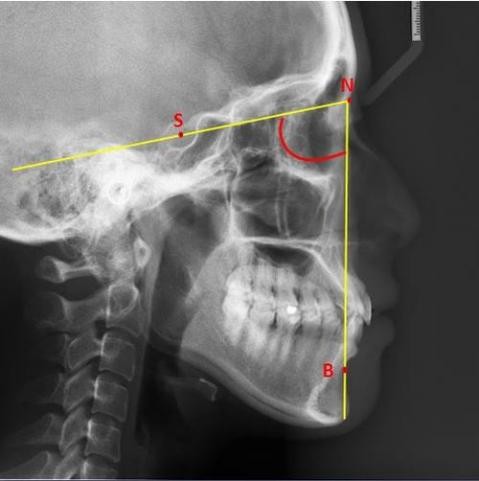

只要牙周条件OK,正畸没有年龄限制。 正畸的原理是利用牙槽骨的重建能力,从而移动牙齿实现矫正。